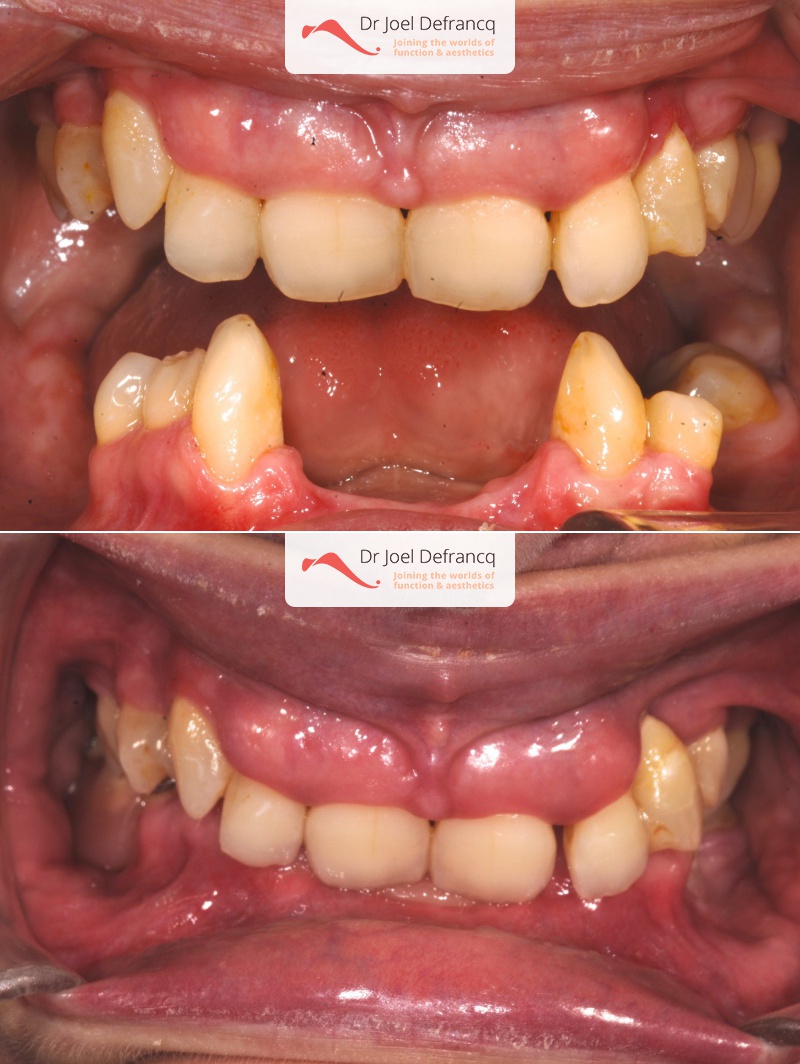

Balera: Extreme deep bite - implants

Dentale diagnose

- Klasse II divisie 2

Behandeling tandheelkundige implantaten

- Vaste tanden op implantaten (bovenkaak)

- Vaste tanden op implantaten (onderkaak)